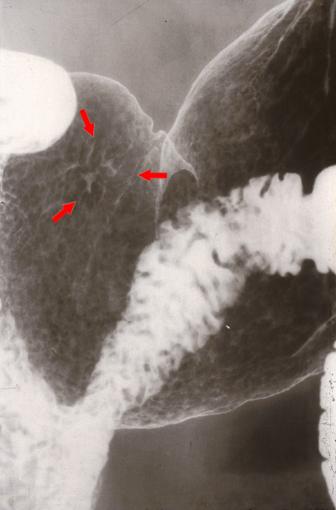

형의 부정으로 진단된 IIc형 조기위암(56세,남성)-1980년대의 증례--

0형(표재형)/IIc형(IIc)

종양의 최대경(밀리미터)

10~14

종양의 심달도

m